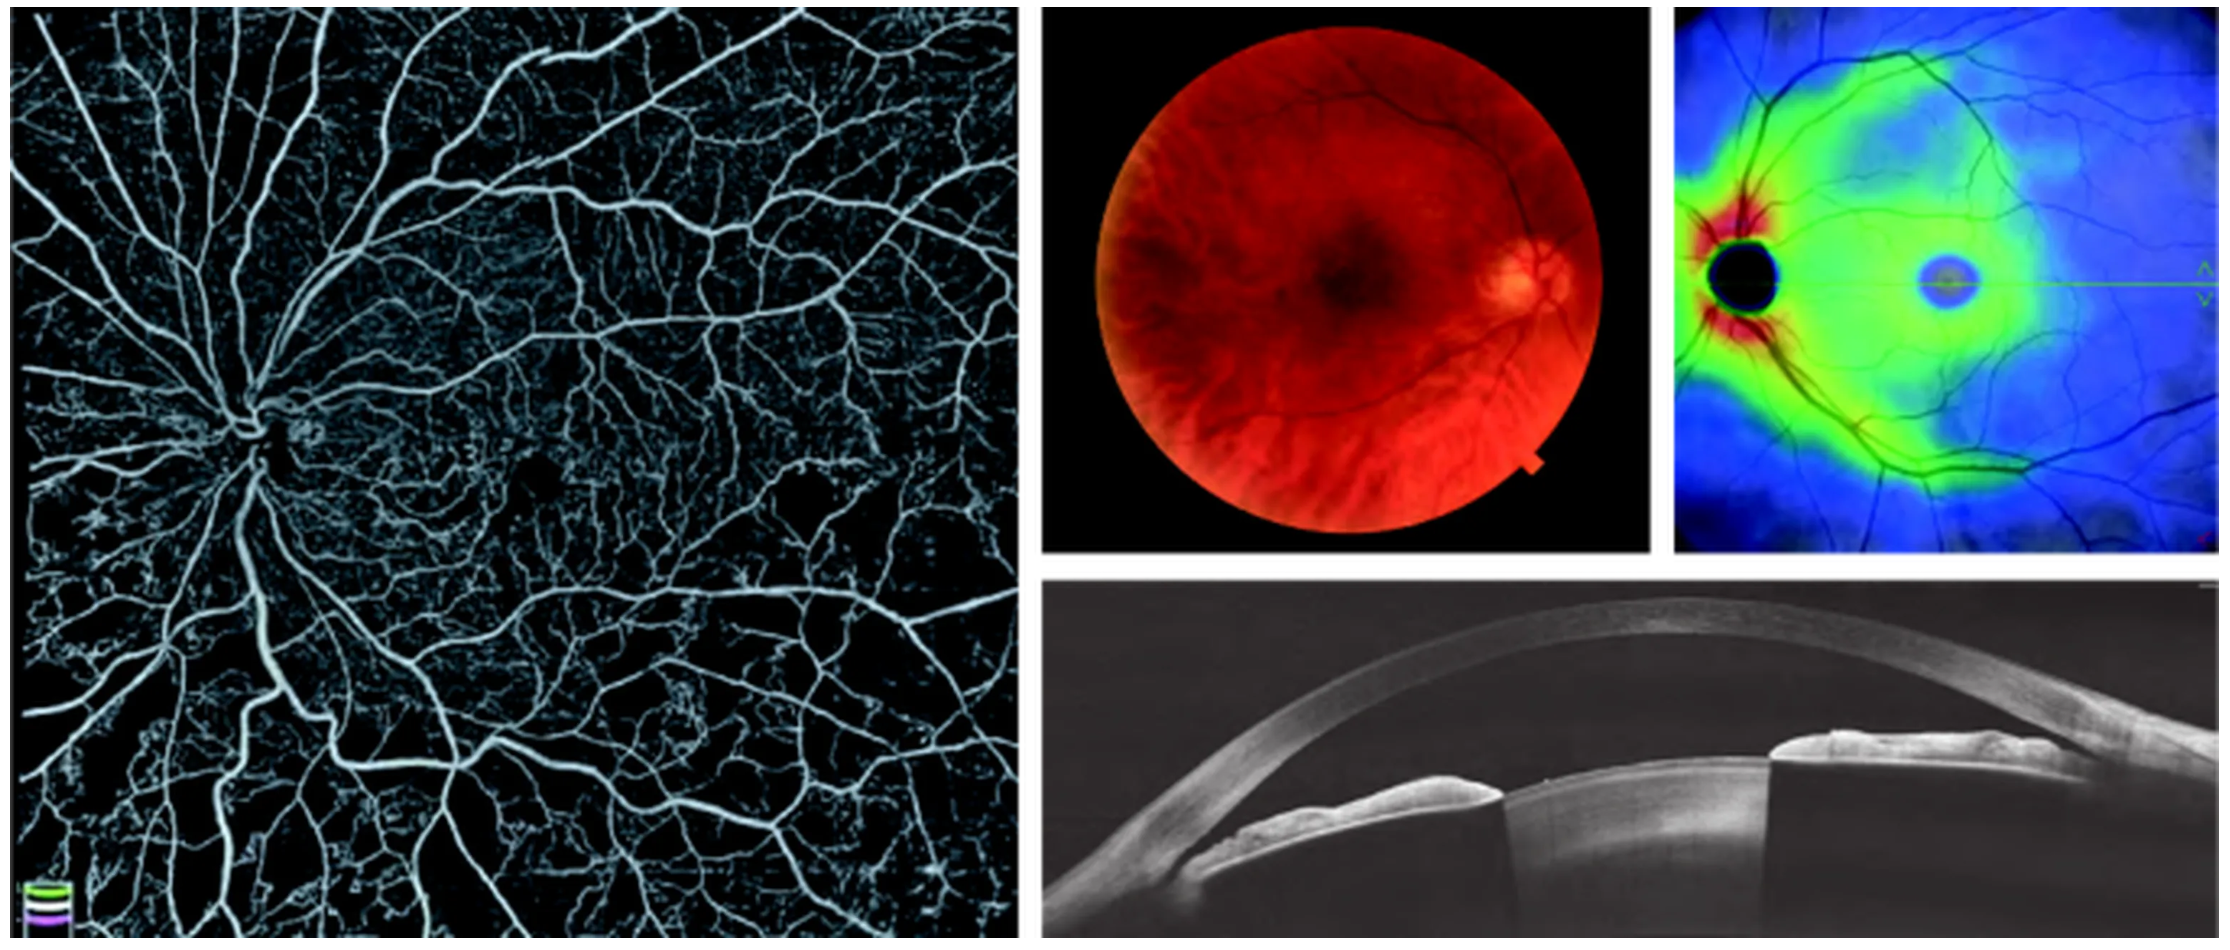

Оптический когерентный томограф Optovue Solix обладает повышенной скоростью сканирования — 120 000 А-сканов в секунду. SOLIX предоставляет множество инструментов для нового поколения борьбы с заболеваниями, которые повышают пропускную способность и обеспечивают превосходный уход за пациентами. В отличие от томографов более ранних поколений ОКТ SOLIX OPTOVUЕ может определять наличие конкрементов и новообразований сосудов сетчатки и хориоидеи, позволяет получать максимально точную послойную визуализацию структур глаза.

- Диапазон сканирования в режиме ангио-ОКТ — от 3х3 до 18х18 мм;

- Размер зоны сканирования в аксиальном направлении — 6,25 мм;

- Программа AngioAnaliticsTM для количественного анализа сосудов сетчатки;

- Полноразмерное сканирование передней камеры;

- Оптическая пахиметрия, картирование эпителия и стромы роговицы в зоне диаметром 10 мм.